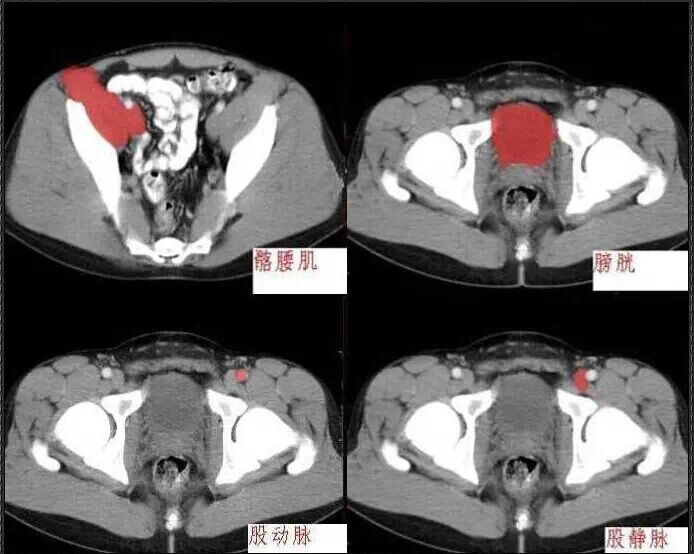

十分钟学会腹部CT解剖(多图)